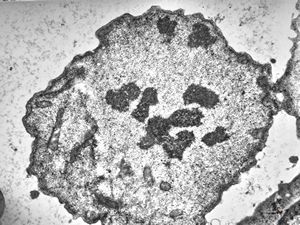

M,62y. | mitosis - plasmocytoma